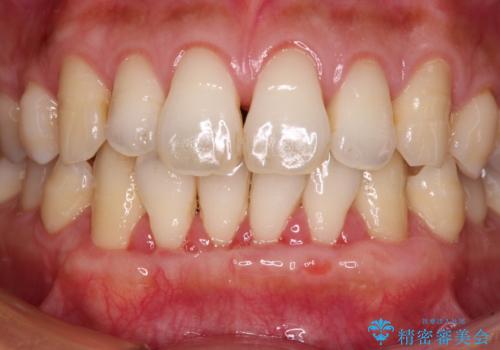

- 年々歯肉退縮が進行することを気にして来院された患者様です。

歯肉が菲薄であることが経年的な進行の原因であることが推察されたため、上顎からの結合組織移植術(CTG)により、歯根の被覆を行うとともに、歯肉の厚みを増すことで将来の退縮リスクを抑制することとしました。

上顎両側から歯肉を採取したたため、術後は痛みや出血で辛い思いをされましたが、1回の処置で満足のいく結果となりました。

根面被覆量も改善できましたが、歯肉の厚みが十分なものとなったことで、今後の歯肉退縮に歯止めをかけることができました。